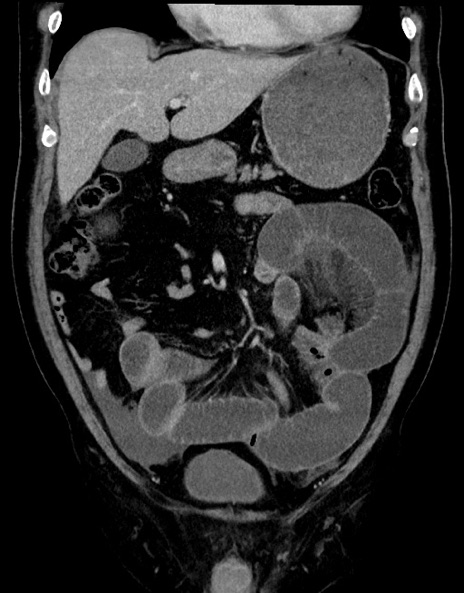

症例15(冠状断像)

【症例】70歳代男性

【主訴】腹痛

【現病歴】今朝から腹痛あり。全体的に痛い。特に左上の方。排ガスが今日はない。冷や汗が出る。

【既往歴】直腸癌術後

【身体所見】左側腹部〜上腹部に圧痛あり。腹膜刺激症状明らかなではない。軽度反跳痛。左下腹部に術後瘢痕あり。

【データ】WBC 7700、CRP 0.02

横断像